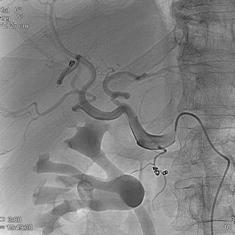

肺动静脉畸形的栓塞(锚定和脚手架技术)

|

|

|

|

|

肺动静脉畸形 |

利用锚定技术将弹簧栓子头端释放到肺动脉其中一支后,其余部分释放到血管内 |

栓塞术后造影 |